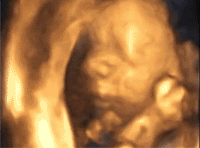

今天我们就精选了一些“胎宝宝”的大片

我要思考下,

要不要给妈妈看我这俊俏的脸蛋呢?

让我好好思考下~

哎呀,人家害羞啦~

不给你看,我要跟你玩躲猫猫,

你再看人家就羞羞啦~

看我这肉嘟嘟的小脚,

以后说不定是大长腿哦~

不要太羡慕我呢~

宝宝们可是很害羞的,过了22-26周

你就看不到羞羞的宝宝了呢

无锡百佳超声影像(四维彩超)提前预约,不用挤也不用久等,还可以保证有足够的时间一对一沟通医生。先进的GE彩色超声设备,可以更清晰地查看宝宝在宫内的发育状况,为筛查宝宝畸形提供更准确的科学依据,还能记录下宝宝此时在宫内的样子,留下0岁写真,意义非凡呀~